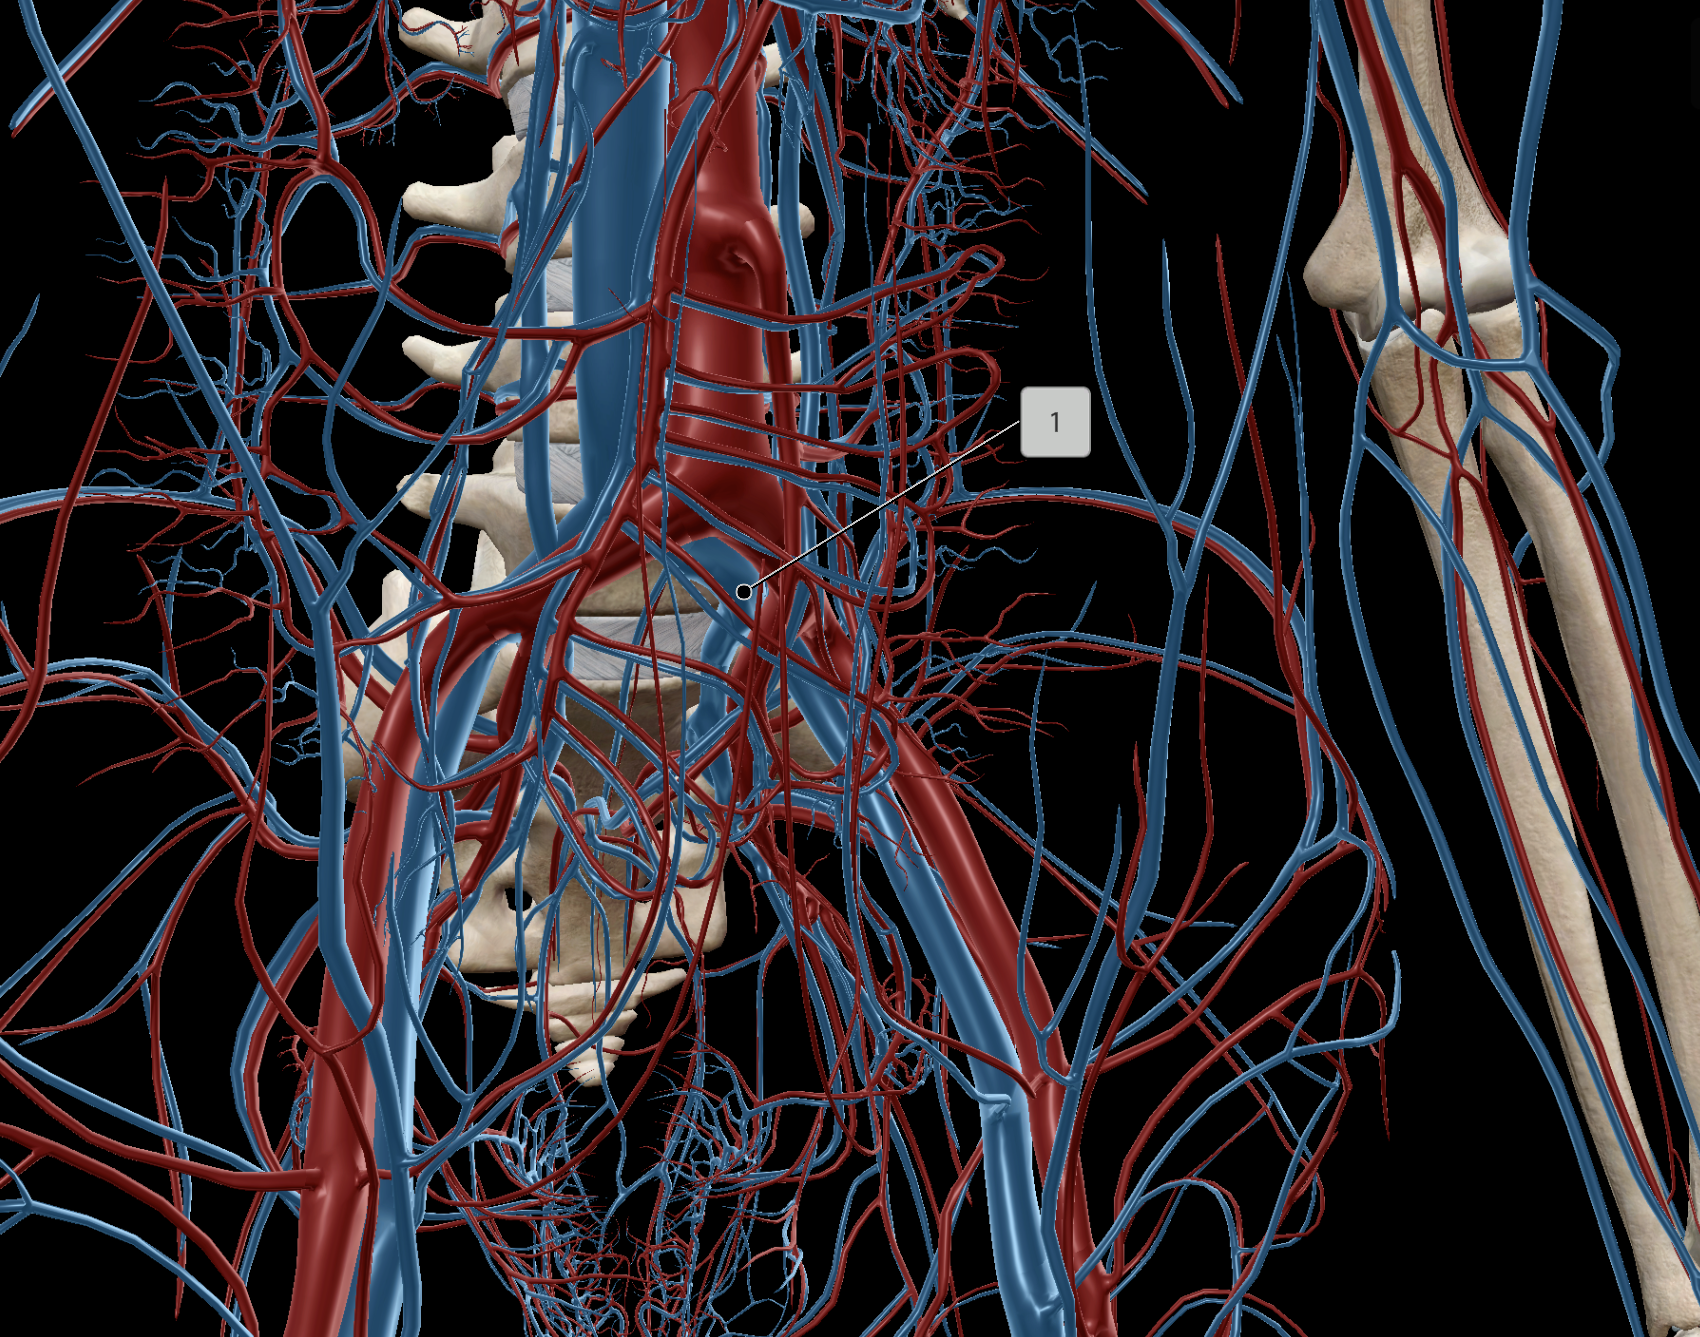

Common Iliac Artery

Internal Iliac Artery

External Iliac Artery

Abdominal Aorta

Common Iliac Vein

External Iliac Vein

Internal Iliac Vein